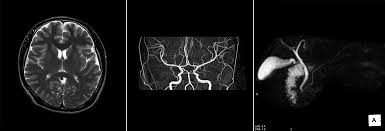

"MRA(Magnetic Resonance Angiography, 자기공명 혈관촬영)"는 MRI를 기반으로 혈관 구조를 영상화한 검사입니다.

- 원리: MRI 기술을 활용하여 혈류 신호를 강조하고, 혈관과 주변 조직을 분리하여 영상화

- 주요 특징: 동맥, 정맥, 혈관 협착, 동맥류 등 혈관 상태 평가에 특화

MRI와 MRA는 모두 자기공명 기반 영상이지만 목적이 다릅니다.

- MRI: 장기, 조직, 연조직의 구조적 이상 확인

- MRA: 혈관 상태 및 혈류 이상 확인

즉, MRI는 조직 중심, MRA는 혈관 중심 진단이 기본 목표입니다.